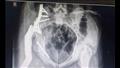

نجح فريق طبي بقسم جراحة العظام بمستشفى أسيوط الجامعي، في إجراء أول جراحة من نوعها لاستئصال ورم من عظمة الإلية ومفصل الحوض لفتاة تبلغ من العمر الخامسة عشر وتركيب مفصل صناعي كامل للحوض.

وقال الدكتور عمرو السيد علي أستاذ جراحة العظام واستشاري الجراحات الميكروسكوبية بجامعة أسيوط، إن المريضة تبلغ من العمر 15 عامًا وكانت تعاني من وجود ورم في عظمة الآلية ومفصل الحوض؛ مشيرًا إلى إجراء العملية الجراحية على مرحلتين في إطار زمني 3 شهور لتجنب البتر.

وجرى في المرحلة الأولى إزالة الورم من عظمة الآلية ونقل الجزء العلوي من عظمة الفخذ لتحل محل عظمة الآلية.

وأوضح الدكتور محمد مهران أستاذ مساعد جراحة العظام واستشاري جراحات تغيير المفاصل الصناعية بجامعة أسيوط، أنه تم بعد إجراء الفحوصات الطبية تم تركيب مفصل صناعي كامل ذو مواصفات خاصة للحوض وذلك دون اللجوء لتثبيت المفصل ولتجنب البتر لهذا الطرف؛ مشيرًا إلى نجاح العملية واستقرار الحالة الصحية للمريضة وتمت متابعتها لحين عودة الحركة للمريضه للصورة الطبيعية.